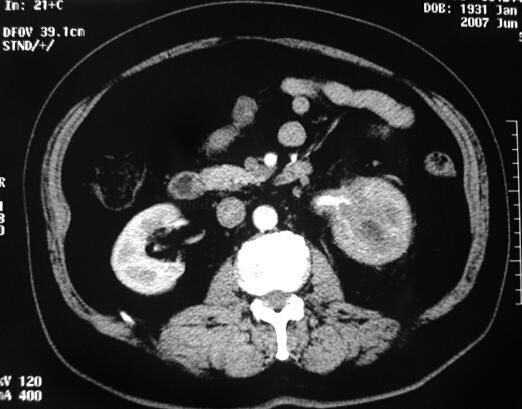

CT(图1):平扫左肾中上极病变,肾皮髓质分解不清、包膜不锐利,肾周脂肪囊增厚,左肾门肾盂结构不清,左输尿管上段实变。增强扫描病变无明显强化,病变边界不清。

图1 CT平扫